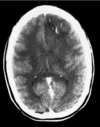

A 28 year-old healthy woman who delivered her second child 10 days ago presents with new onset headache, lethargy, and confusion. She has no focal deficits. A noncontrast head CT is obtained and shown below. What is the most appropriate definitive treatment for this patient? A. Endovascular embolization B. Recombinant activated Factor VII C. Intravenous heparin infusion D. Craniotomy for hematoma evacuation E. Observation only

C. Intravenous heparin infusion

60

A 48 year-old man with a right middle cerebral artery distribution infarction. Despite aggressive medical and endovascular therapy, the artery remains occluded. Two days later he has a decline in mental status. His head CT is shown. What is the most likely explanation for the patient’s new neurological deterioration? A. Occlusive hyperemia B. Reperfusion syndrome C. Hemorrhagic conversion D. Cerebral edema E. Normal perfusion pressure breakthrough

D. Cerebral edema